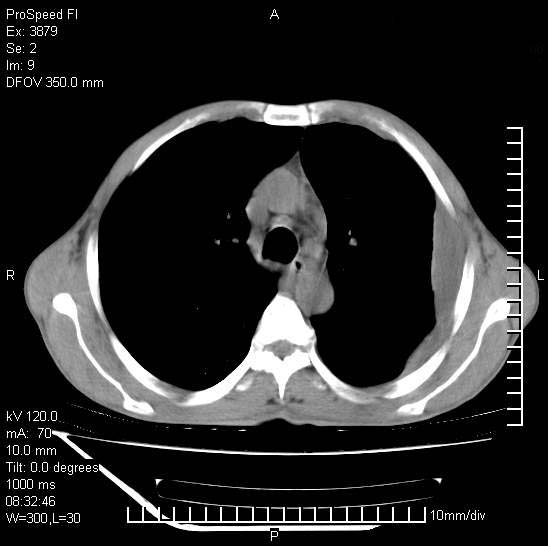

以下是引用37度在2008-6-6 11:20:00的发言:[br]1.包裹性积液,多考虑结核性;[br]2.穿刺术后改变。

以下是引用312nanyang在2008-6-6 15:12:00的发言:[br]基本支持楼主意见[br]疑问?左下肺支气管旁的软组织(16层)密度怎么解释?淋巴结还是斜裂胸膜增厚所致?能否增强进一步检查